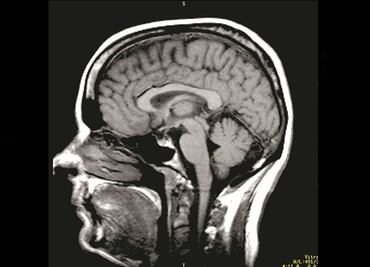

Será el primer humano en prestarse a una operación en la que su cabeza se trasplantaría a otro cuerpo

Sufre atrofia muscular espinal, una grave enfermedad genética